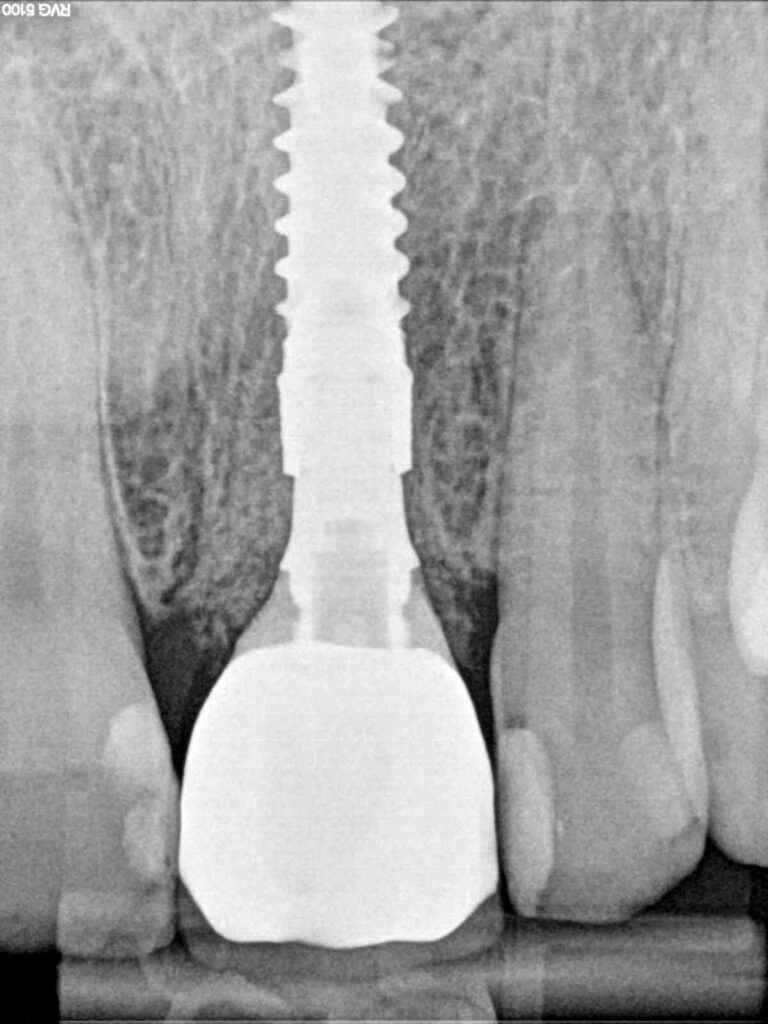

Fig. 5: Radiograph showing implant and implant-supported provisional crown 21